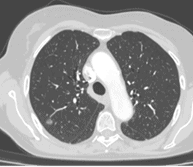

Cette technique nécessite un fibroscope bronchique, c’est-à-dire une caméra miniaturisée permettant d’explorer le poumon et les bronches de l’intérieur, par les voies naturelles.

La minisonde est une sonde de 2 mm qui s’insère dans le fibroscope permettant compte tenu de sa petite taille d’ aller plus loin dans les bronches de petit calibre. Cette minisonde est elle-même équipée d’une sonde d’échographie, miniaturisée à l’extrême, permettant d’examiner le poumon de l’intérieur.

Ainsi des cancers à des stades plus précoces qu’auparavant peuvent être repérés et opérés.